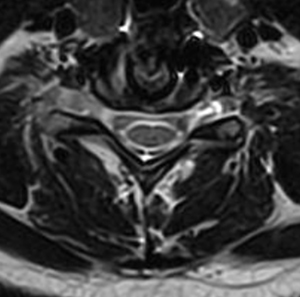

She underwent a minimally invasive anterior cervical discectomy and fusion after removing the herniated disc. A MRI shows resolution of the herniated disc.